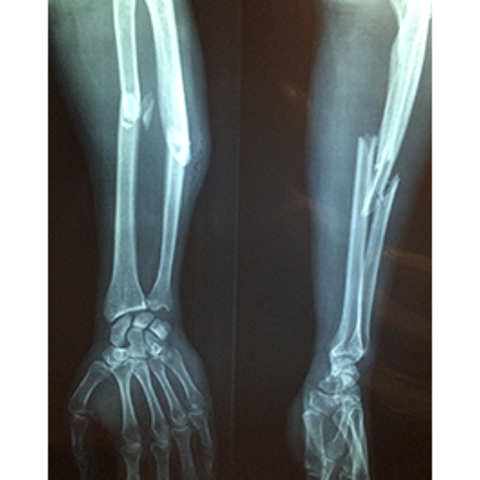

De tyska forskarna hänvisar till flera undersökningar som har visat att typ 1-diabetiker har en försämrad bentäthet vilket gör skelettet skört och att läkningsprocessen tar längre tid. Långvariga höga blodsocker försämrar bentätheten.

”Benskörhet har pekats ut som en komplikation vid diabetes som ofta resulterar i sjukhusvård, handikapp, lägre livskvalitet och för tidig död.” skriver forskarna och fortsätter. ”Detta kan dock förebyggas under livets alla faser.”

De påpekar också att frakturrisken är högre bland typ 1- än bland typ 2-diabetiker. Till exempel är höftfrakturer fem gånger vanligare bland typ 1-diabetiker.